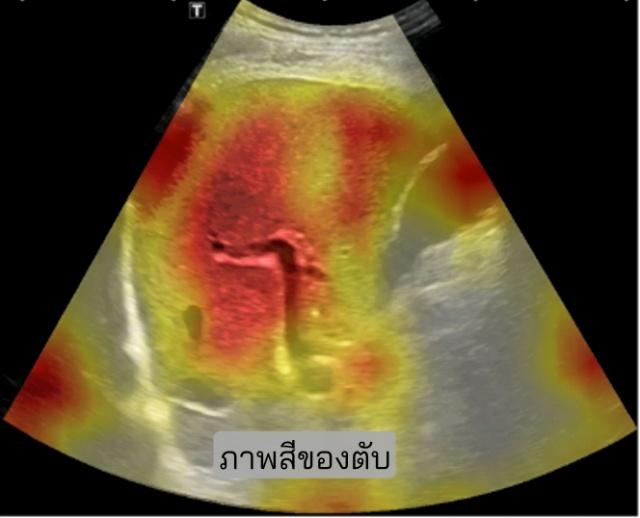

SmartLiva ทำงานโดยอัปเกรดภาพอัลตราซาวด์ขาวดำธรรมดา อัปโหลดผ่านเว็บได้ทั้งบนคอมพิวเตอร์หรือแท็บเล็ต ระบบจะปรับภาพให้ชัด คัดเฉพาะบริเวณเนื้อตับที่ต้องวิเคราะห์ ทำให้ภาพดูเข้าใจง่ายขึ้น ด้วยการไฮไลต์เป็นสี (เช่น ตับเป็นสีแดง ไขมันเป็นสีเหลือง) เพื่อเห็นความผิดปกติได้ทันที AI จะประเมิน 3 เรื่องพร้อมกัน คือ ระดับพังผืด/ความแข็งของตับ (F0–F4), ตรวจหาความผิดปกติของเนื้อเยื่อ เช่นถุงน้ำหรือมะเร็งตับ ตรวจหาพยาธิใบไม้ตับ ทั้งประมวล วิเคราะห์ สรุปผลออกเป็นรายงานพร้อมภาพประกอบและคำอธิบายที่คนทั่วไปเข้าใจได้